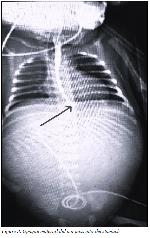

A one-day-old female (36+5 weeks gestation, birth weight of 2070 g) was born via cesarean section with spinal anesthesia; her mother was 31 years old, gravida 7, parity 2, abortion 4. She was admitted to the newborn intensive care unit due to extensive skin lesi-ons and antenatal polyhydramnios, and there was no intraabdominal gas was seen on X-ray (Figure 1).

Click Here to Zoom

Figure 1: Postnatal first day no gas on abdominal X-Ray examina-tion.